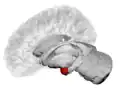

MRI coronal view of the amygdala

MRI coronal view of the right amygdala